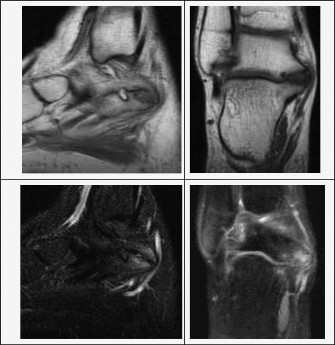

التصوير المتقدم بالأشعة المقطعية والرنين المغناطيسي

عندما تكون الأشعة السينية غير حاسمة، أو عند الاشتباه بقوة في ائتلاف عظام الرسغ، يوصي الأستاذ الدكتور محمد هطيف بالتصوير المتقدم.

- الأشعة المقطعية (CT Scan): تُعد الأشعة المقطعية الطريقة الأكثر تحديدًا لتشخيص ائتلاف عظام الرسغ، خاصة لتقييم الجسور العظمية. توفر صورًا ثلاثية الأبعاد مفصلة للعظام، مما يسمح بتحديد حجم وموقع الائتلاف بدقة.

- الرنين المغناطيسي (MRI Scan): يُعد الرنين المغناطيسي أكثر دقة في تشخيص الائتلافات الجزئية العظمية، والائتلافات الليفية أو الغضروفية التي قد لا تظهر بوضوح في الأشعة المقطعية. كما يمكنه تقييم أي تغيرات تنكسية في المفاصل المحيطة.

الشكل 10-56: صور الأشعة المقطعية الجانبية (يسار) والتاجية (وسط) وإعادة البناء ثلاثي الأبعاد (يمين) لكاحل مريضك.

الشكل 10-57: صور الرنين المغناطيسي السهمية (يسار) والتاجية (يمين) (T1: الصف العلوي؛ T2: الصف السفلي) لكاحل مريضك.